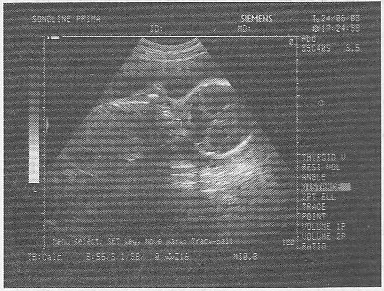

1.女,26歲,停經(jīng)23周產(chǎn)前B超檢查如圖,結(jié)合超聲圖像,最可能的診斷為

A.前置胎盤

B.正常晚期妊娠

C.胎兒畸形,腦積水

D.胎兒畸形,腹壁裂

E.脈絡膜囊腫

正確答案:C 解題思路:側(cè)腦室增寬,呈無回聲區(qū),>2cm,胎兒雙頂徑增寬。